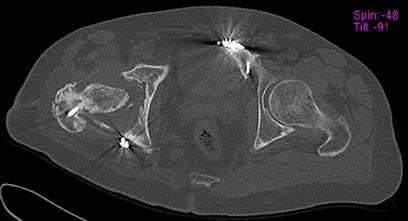

Пациент 49 лет, паровозная травма 23.2.2006, получил вертикальная

нестабильное повреждение таза, разрыв левого крестцово-подвздошного

сочленения, перелом лонной, седалищной костей слева, T-образный

оскольчатый перелом правой вертлужной впадины с переломом заднего

края, вывих правого бедра, посттравматическая пояснично-крестцовая

плексопатия с обеих сторон, паралич мышц правой голени.

В день травмы - вправление вывиха, скелетное вытяжение, 14.3.2006

чрескостный остеосинтез таза. 20.4.2006 остеосинтез правой вертлужной

впадины пластинами, осложнившийся нагноением межмышечной гематомы

правой ягодичной области. Получал консервативное лечение, было

достигнуто полное заживление раны. 24.7.2006 введены илиосакральные

винты слева. С декабря 2006 года и по настоящее время ходит на

костылях без опоры на правую ногу. Планируется THA. Помогите

определиться с вариантом костной пластики? И какую укрепляющую

конструкцию использовать?